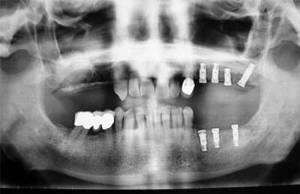

La incorporación de la implantología en la práctica odontológica ha representado un gran avance para la rehabilitación-restauración de la perdida de los dientes. Antes se instalaban prótesis apoyadas en otros dientes o sobre la mucosa bucal produciéndose todo tipo de complicaciones. Los implantes dentarios son fijaciones (tornillos) de titanio con superficies bioactivas que se colocan en los maxilares (intraóseos), imitando una raíz dentaria aunque su comportamiento es diferente.

Las fijaciones o implantes se pueden instalar en el hueso alveolar de forma inmediata (tras la extracción del diente) o de forma diferida (al cabo de unos meses cuando la mucosa y el hueso este cicatrizado). Igualmente la prótesis puede colocarse de forma inmediata (es una prótesis provisional y normalmente fuera de oclusión) o de forma diferida (cuando el implante esta osteointegrado: 2-4 meses en la mandíbula y de 4 a 6 meses en el maxilar superior).

Normalmente se prefieren colocar prótesis fijas sobre los implantes (atornilladas o cementadas) aunque también pueden indicarse prótesis removibles (de poner y quitar) pero que están apoyadas sobre los implantes y no sobre otros dientes o sobre la mucosa bucal y el hueso alveolar.